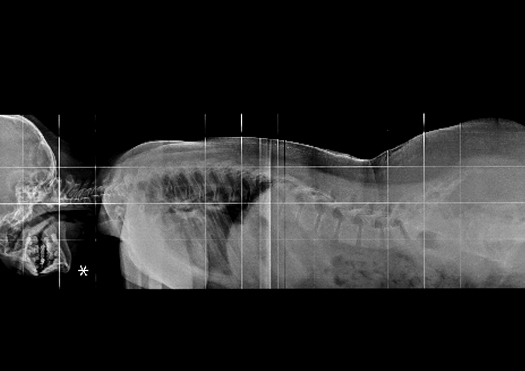

Rayos X

Producen una imagen cuando un haz de rayos X, atraviesa el cuerpo y los diferentes tejidos atenuarán o absorberán cierta cantidad de rayos X, pero habrá algunos que salen del cuerpo y llegan al detector de radiación para generar una imagen.